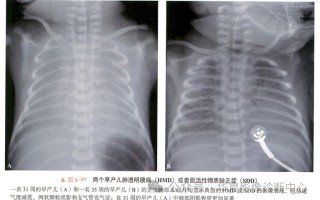

新生儿健康护理 新生儿肺透明膜病有哪些典型临床表现? 核心临床表现呼吸系统症状(最突出和最早的表现)这是NRDS最核心、最典型的症状群,通常在出生后2-6小时内出现,且进行性加重,呼吸急促: 这是最早、最常见的症状,表现为呼吸频率明显增快,通常>6... 99ANYc3cd6 2025-11-29 0 #新生儿肺透明膜病症状表现 #早儿肺透明膜病典型体征 #新生儿透明膜病临床表现